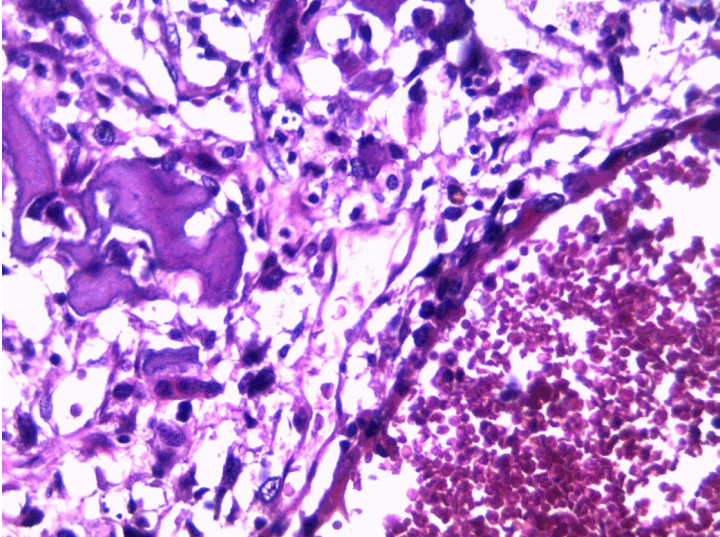

At the pathology laboratory, we received a piece of the left lower limb amputation. (Figure 2) We opened it. Gross examination of the resected distal femur revealed a 22x5 cm intramedullary multicystic hemorrhagic destructive tumor with cortical destruction and extension into the adjacent anterior and posterior soft tissues. The latter component of the mass was larger than the intraosseous tumor. (Figure 3) The articular surface was not involved. We cut the femur in its longest axis with electric saw. (Figure 4) Fixation in 10% neutral buffered formalin for 48 hours and decalcification of bone with nitric acid were performed. Slice of bone section was included in full. Many specimens from soft tissues and the surgical margins were also taken. Microscopic view of histological specimens of tumor stained with hematoxylin andeosin showed prominent blood filled cysts with malignant stroma in septa separating cysts. (Figure 5) (Figure 6) It contained atypical tumor cells oval or round of variable size with osteoblast-like multinucleated giant cells and a variable amount of immature osteoid. (Figure 7) (Figure 8) (Figure 9) (Figure 10) (Figure 11) (Figure 12) Numerous mitotic figures were noted (Figure 13). The tumor was located at 6 cm from the bone limit and 2 cm at the edge of the soft tissues. The resection margins were negative. The marrow, scooped and submitted separately, was negative.

Figure 5: Low magnification showing large blood-filled cystic spaces with septa composed of loose hemorrhagic tissue with sarcomatous cells (H&E stain, x400).

Figure 6: Medium-power magnification shows cystic spaces without lining surrounded by septa containing highly atypical malignant cells (H&E stain, x100).